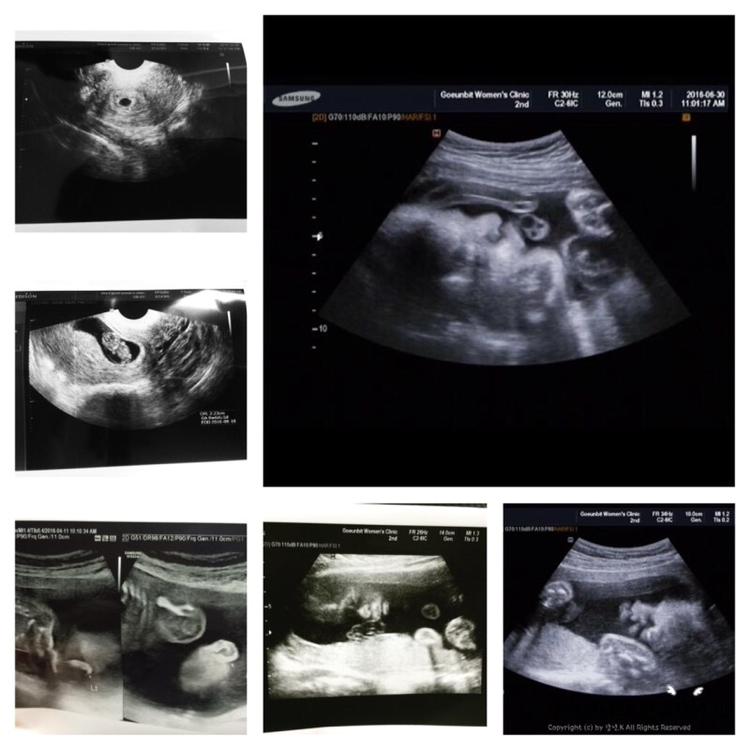

이 날 병원을 다녀온 뒤 산모수첩을 정리하였다. 천천히 하나하나 아이의 작고 작았던 그날의 초음파 사진들을 보는데 조그만했던 세포가 어느새 손이 생기고 발이랑 척추도 생기고 또 심장도 뛰고 이젠 입도 오물오물 거리 고하는 걸 보니 어쩐지 기분이 묘해졌다. 이렇게 잘 크고 있는 아이를 보니 기특하기도 하면서 말이다. 이제 정말 한 달도 남지 않았는데 그저 난 아이가 건강하게만 태어났으면 좋겠다. 그것 말곤 더 이상 바랄 게 없다. 하... 이제 아이 만날 날을 기다리며 출산 가방도 조금씩 싸놔야겠다.